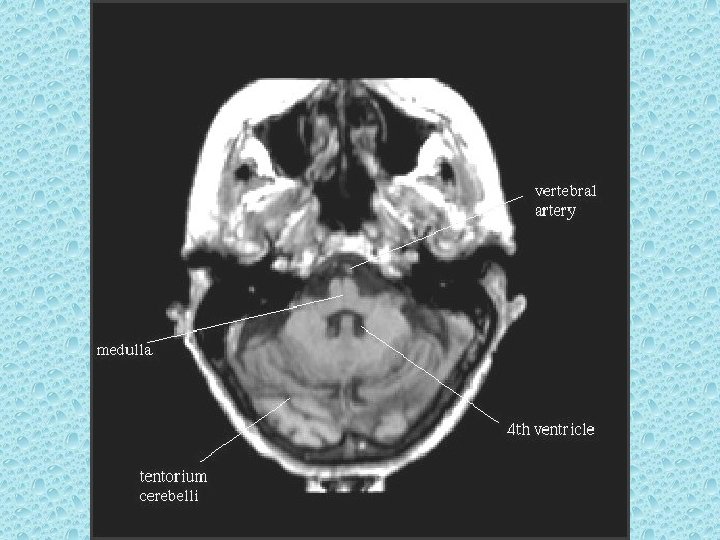

POSTERİOR FOSSADA BULUNAN YAPILAR • • • Serebellum Beyin sapı 4. ventrikül Vermis Transvers ve sigmoid sinüs

VENTRİKÜLLER • Lateral ventriküller: frontal, oksipital ve temporal hornlar, korpus ve atrium • Foramen monro • 3. Ventrikül • Akuaduktus silvii • 4. Ventrikül • Foramen Lucka (çift) ve magendi (tek)

KAFA İÇİNİ BESLEYEN ARTERLER • Bilateral karotid sistem: İnternal karotid arter - A. oftalmika, a. kommunikans posterior, a. koroidea, a. serebri anterior ve media • Vertebrobaziler sistem: Vertebral arterler ve baziller arterlerden oluşur - A. Serebellaris posterior inferior (pica), anterior inferior (aica), a. serebellaris superior, a. serebri posterior